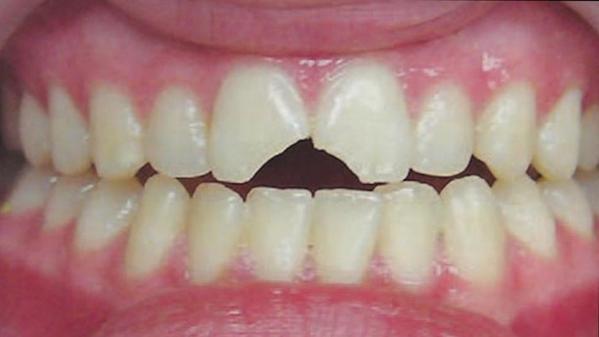

Image Gallery

Pictures That Speak